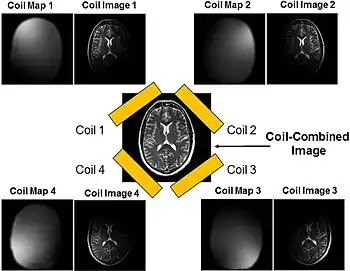

Parallel imaging

Parallel imaging involves the addition of multiple coils surrounding the target with each coil acquiring a fraction of the total image. Because modern GPUs have parallel processing capabilities, they can reconstruct each portion of the image simultaneously. Therefore, the more coils used, the faster the acquisition of the MR images.[15]

Certain image reconstruction algorithms used alongside parallel imaging address the potential issues that can arise from undersampling the k-space. SENSitivity Encoding (SENSE) is a method that reconstructs the partial k-space data from each coil and combines the partial images into the final scan in the spatial domain.[23] Coil sensitivities must first be acquired either before the actual imaging or during the imaging process. During the rest of imaging, the k-space is undersampled to skip every other line, resulting in a ½ FOV.

As a two-point example, pixels on the original aliased images can be “unfolded” through the following equations to give the final scan:

for two points, and , in the final image. and denote the image signal for the aliased image. and are the sensitivity values for coil 1 at points and , respectively, and and are the sensitivity values for coil 2 at points and , respectively.[23]